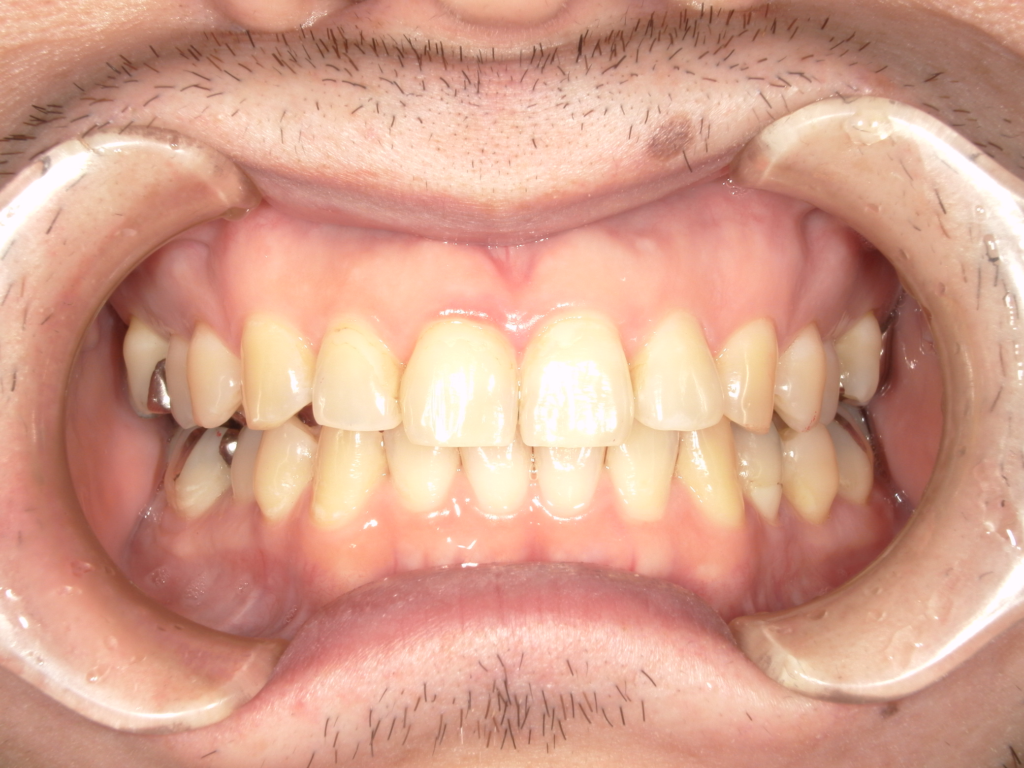

Y様インプラント実例 #44

左の上下の奥歯をインプラントで治療しています。

左下の奥歯は歯を抜くのと同時にインプラントの埋め込みを行っています。

被せものは上下、セラミックスで作っています。

治療前

治療後